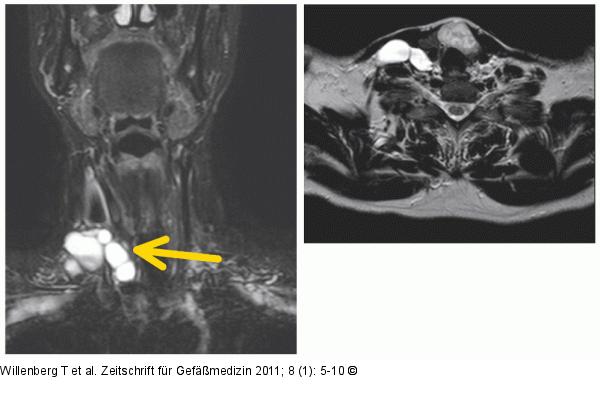

Abbildung 5: MR Malformation MR mit Darstellung einer großen lymphatischen, makrozystischen Malformation zervikal rechts. |

MR mit Darstellung einer großen lymphatischen, makrozystischen Malformation zervikal rechts. |